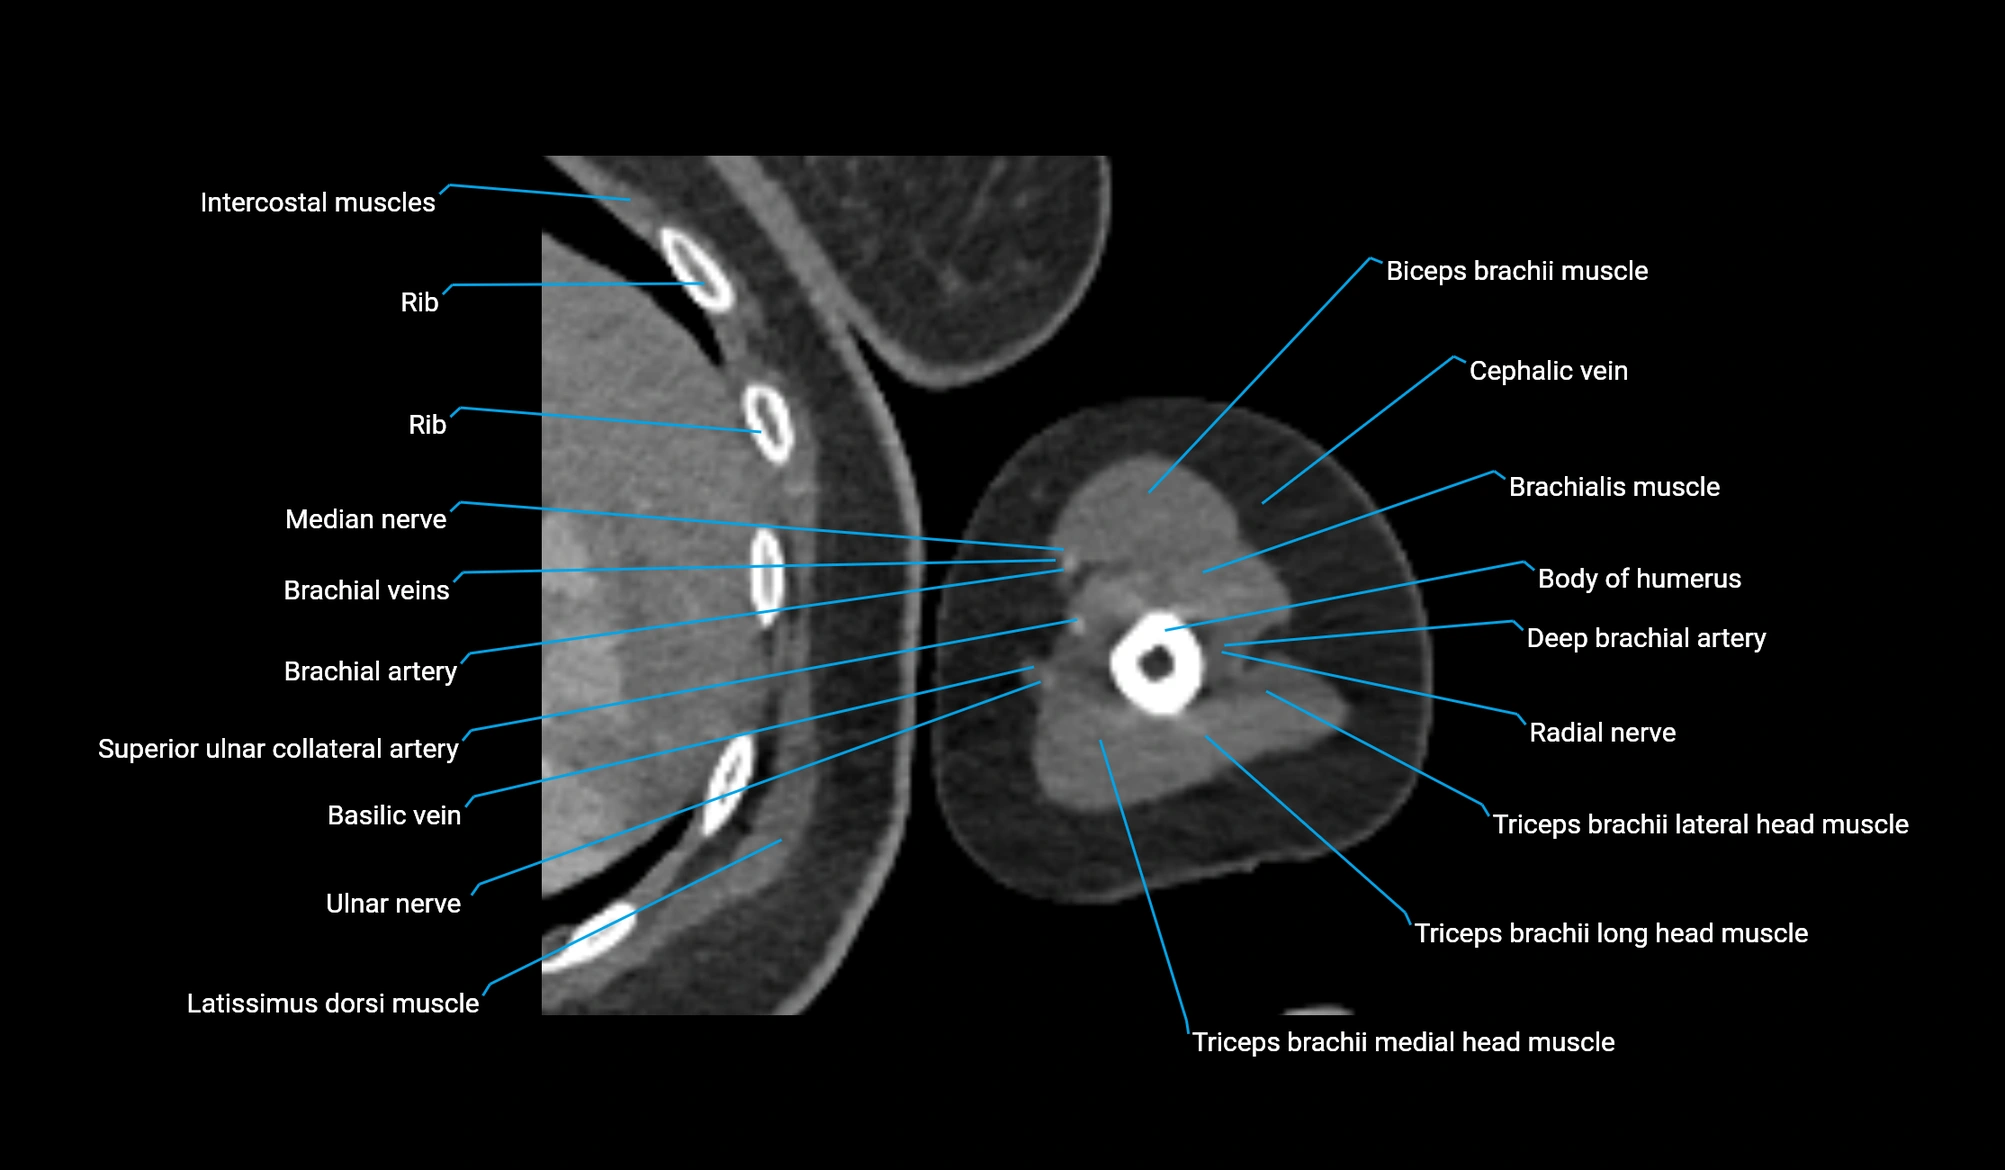

- Basilic vein

- Body of humerus

- Brachial artery

- Brachialis muscle

- Cephalic vein

- Deep brachial artery

- Lateral head of triceps brachii muscle

- Long head of triceps brachii muscle

- Medial head of triceps brachii muscle

- Median nerve

- Radial nerve

- Superior ulnar collateral artery

- Triceps brachii muscle

- Ulnar nerve